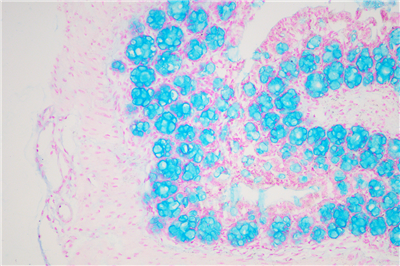

阿利新蓝(又称阿尔辛蓝﹑爱先蓝等)和PAS技术联合使用可鉴别同一组织中的中性黏蛋白和酸性粘蛋白。这种技术也常用作广泛检测黏蛋白的手段,切片先经标准阿利新蓝染色再使用PAS技术。阿利新蓝可将唾液黏蛋白﹑硫黏蛋白和蛋白多糖染成蓝色。PAS技术可将中性黏蛋白染成深红或紫红色,同时将既含中性黏蛋白又含酸性黏蛋白的组织和细胞染成深浅不同的紫色,这是由于阿利新蓝与Schiff试剂结合并发生反应。上述染色常可出现在含有中性黏蛋白和唾液黏蛋白的笑场杯状细胞中。阿利新蓝的染色原理在于是类铜钛花青染料,这种阳离子染料与酸性基团结合,也即阿利新蓝与组织内含有的阴离子基团如羧基和硫酸根形成不溶性复合物。分子中带正电荷的盐键与酸性粘多糖物质中带负电荷的酸性集团结合形成不溶性的复合物而呈蓝色,再与PAS进行复合染色,就能显示三种不同黏液物质成分。